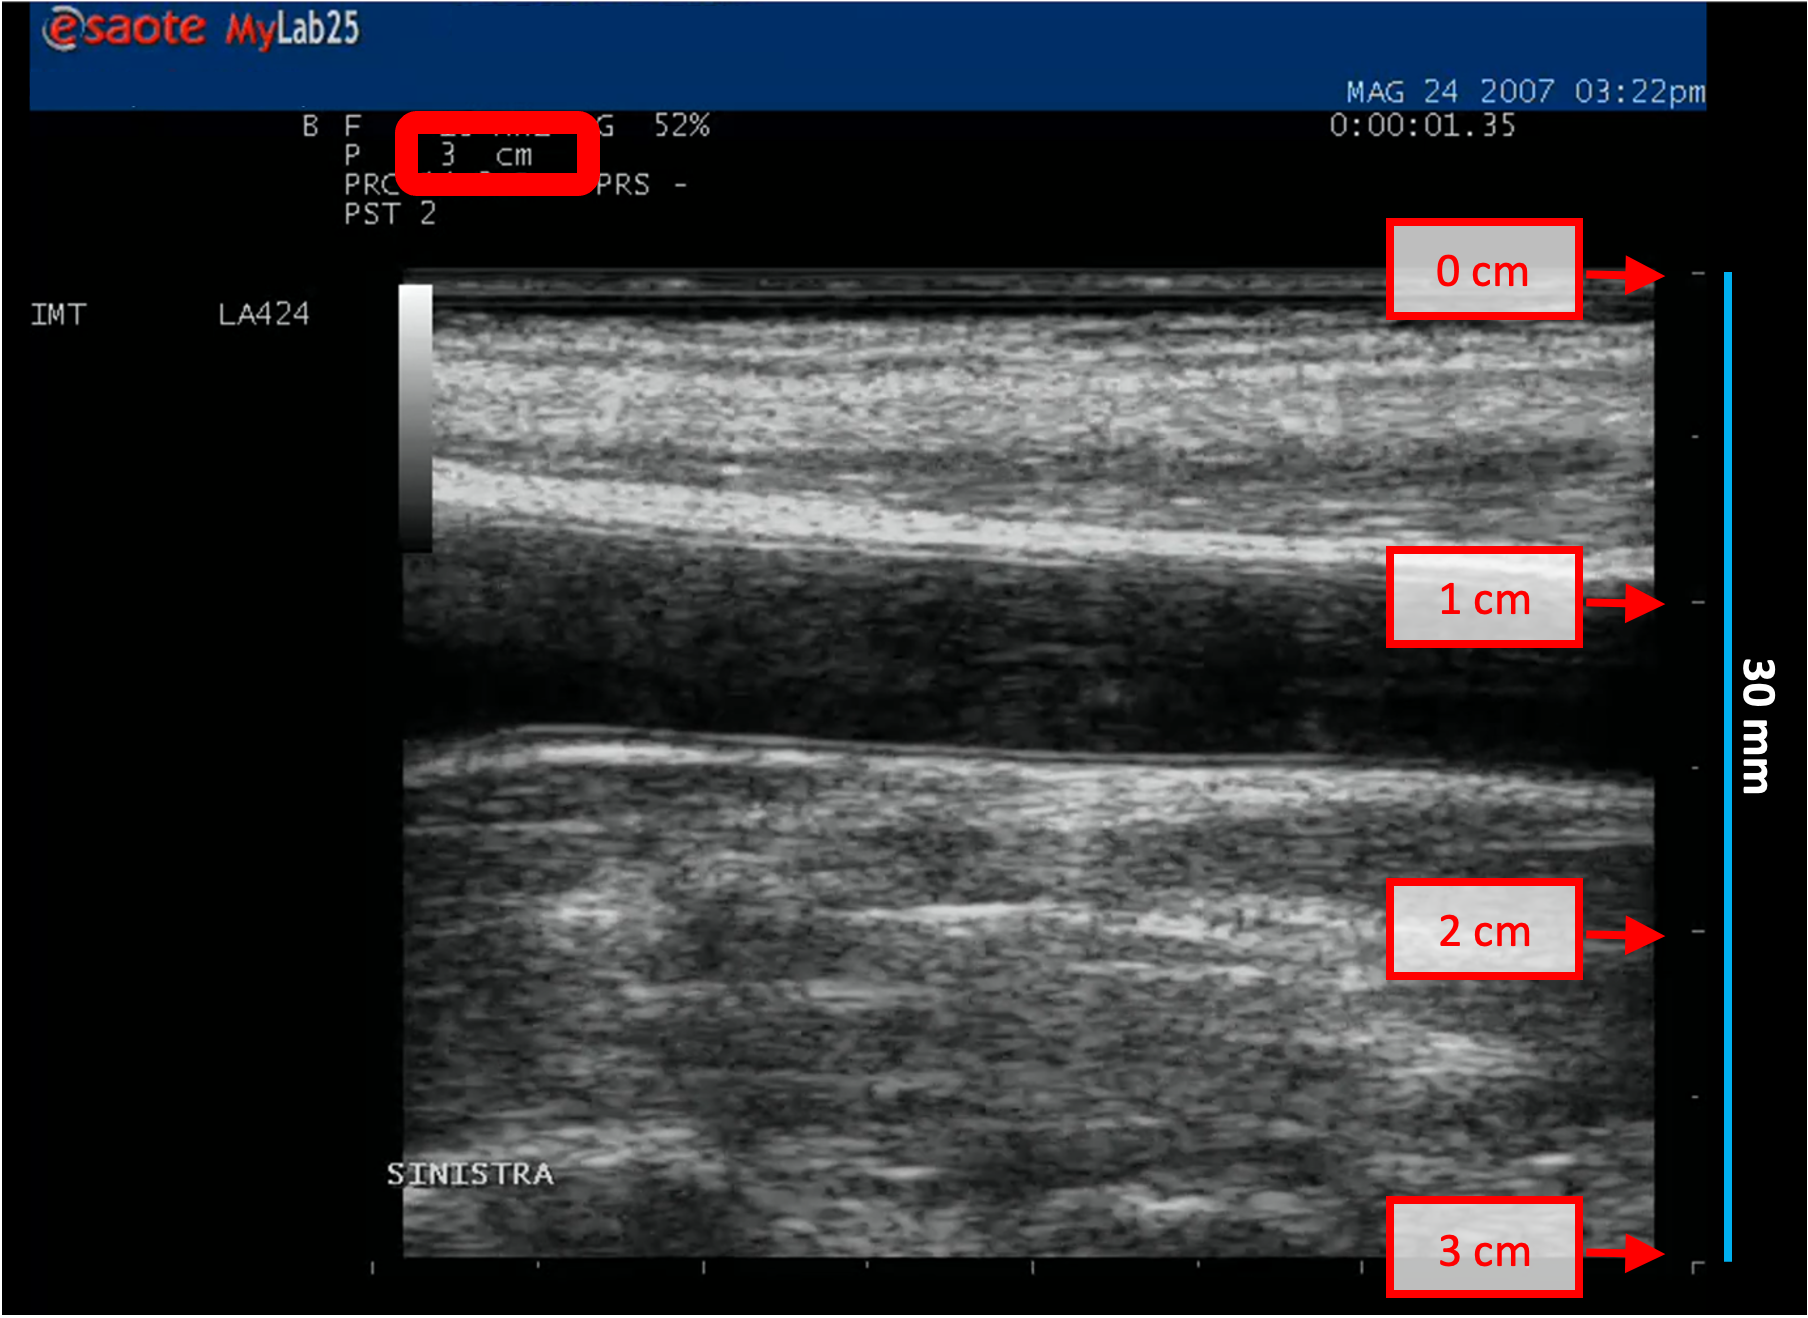

• Repérer, sur l'image ultrasonore, une plage de distance connue (30 mm dans l'exemple de la figure).

Exemples d'étalonnage en mode B

Les images suivantes présentent des exemples d'étalonnage de l'image en mode B. Les éléments graphiques en rouge indiquent où trouver les informations relatives à la profondeur de l'image échographique.